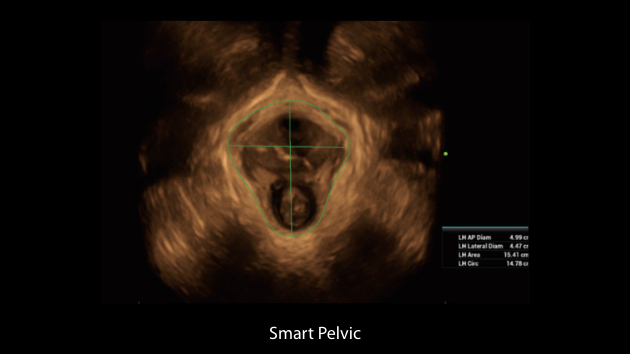

Gambar Klinis